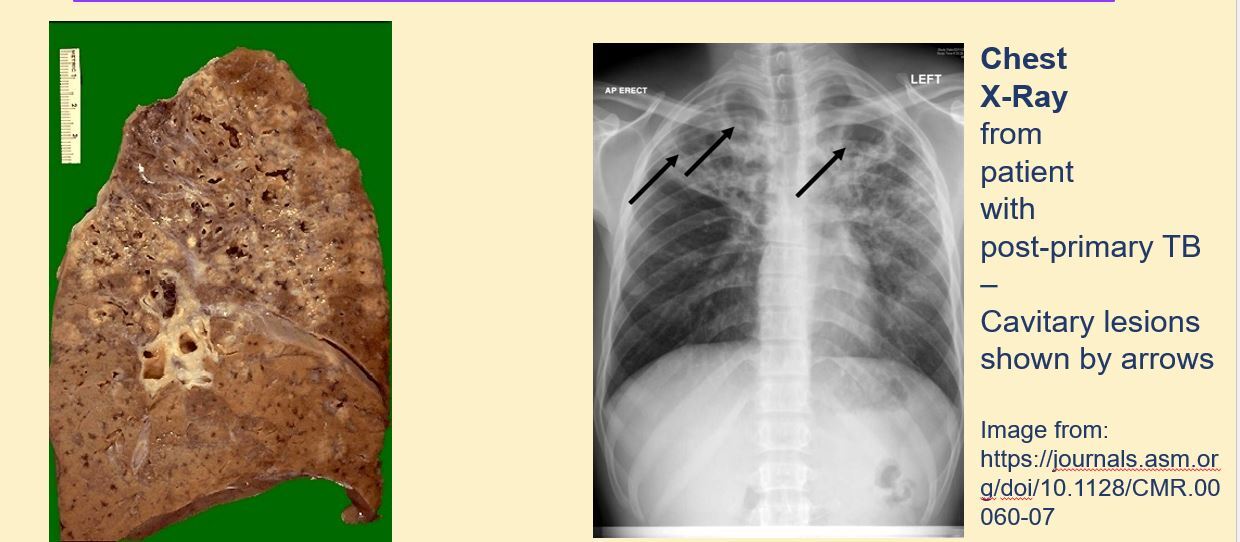

why is post-primary TB worse

A

Q

TB signs

pyrexia

possible chest crackles

CXR abnormality

if large cavitations, hyperresonance